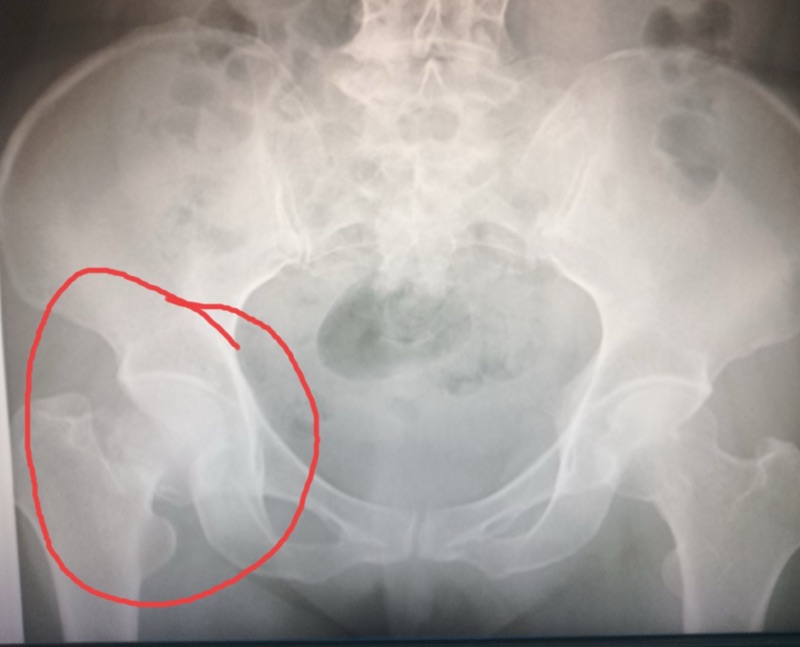

กระดูกสะโพกหัก (Femoral neck fracture) เป็นอุบัติเหตุที่พบได้บ่อยในผู้สูงอายุ โดยเฉพาะในผู้ที่เป็นโรคกระดูกพรุน การพลัดตกหกล้มเพียงเล็กน้อยก็สามารถทำให้กระดูกหักได้ ส่งผลกระทบต่อคุณภาพชีวิตอย่างมาก เพราะอาจทำให้เดินไม่ได้ เจ็บปวด และเสี่ยงต่อภาวะแทรกซ้อน เช่น ลิ่มเลือดอุดตัน ปอดอักเสบ หรือแผลกดทับ

1. การผ่าตัดยึดตรึงกระดูก (Internal Fixation)

• ใช้สำหรับกระดูกหักที่ไม่เคลื่อนออกจากตำแหน่งมากนัก

• ศัลยแพทย์จะใช้โลหะ เช่น สกรู หรือเพลทยึดตรึงกระดูกให้ติดกัน

• เหมาะสำหรับผู้ป่วยที่อายุน้อยกว่า 65 ปี หรือยังมีสุขภาพแข็งแรง

2. การเปลี่ยนข้อสะโพกบางส่วน (Hemiarthroplasty)

• เหมาะสำหรับกระดูกหักที่เคลื่อนจากตำแหน่ง หรือในผู้สูงอายุที่มีกระดูกพรุนมาก

• ผ่าตัดเปลี่ยนเฉพาะหัวกระดูกต้นขาโดยใช้วัสดุเทียม

• ลดความเสี่ยงของภาวะกระดูกขาดเลือด (Avascular necrosis)